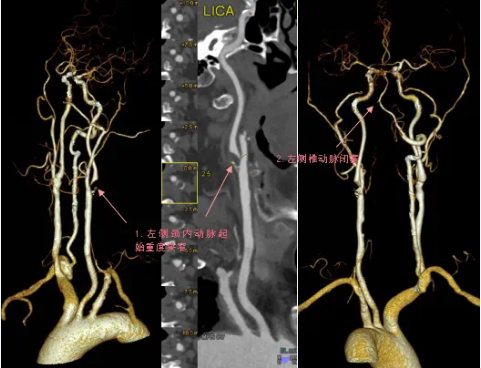

70岁的程爷爷,突然出现右侧肢体无力,右上肢勉强抬举,右下肢不能撑重,还有口角歪斜症状,到蜜桃视频-麻豆蜜桃 就诊检查,医生了解病情后,随即为老人开具了头颈部CTA检查,检查结果显示程爷爷的左侧颈内动脉起始部重度狭窄,几近闭塞;左侧椎动脉重度狭窄,局部闭塞。

头颈部CTA即头颈部CT血管造影,是一项非创伤性头颈部血管成像技术,具有快速、无创、并发症相对较少等优点。

头颈部CTA可以清楚地显示由主动脉弓向头部发出的动脉血管及其分支,对于血管狭窄、闭塞、动脉瘤、头颈部动脉钙化斑块程度,以及脑卒中等疾病的诊断有重要价值,目前已被广泛应用于脑血管病检查。